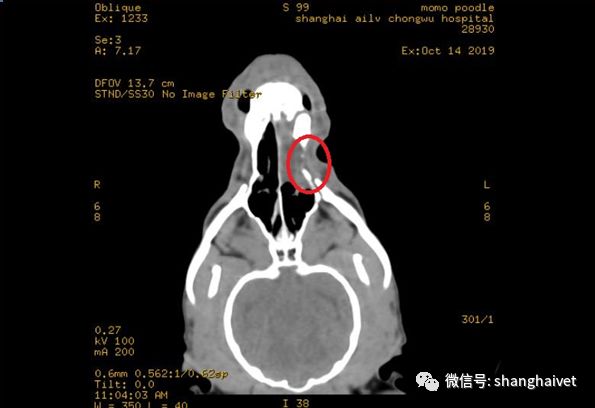

▲CT扫描显示左侧上犬齿及前臼齿异常

CT 鼻腔扫描后,诊断为左侧上犬齿及前臼齿齿根瘘道并发鼻腔内渗出,影像结果显示左侧犬齿、前臼齿齿槽部分结构消失,齿根位置已经与鼻腔相通,邻近的部分硬腭也已经部分溶解消失,在异常的病灶周围有明显的液性不透性的渗出影像,范围从左侧鼻腔头侧到中部,未跨越鼻中隔到达对侧鼻腔。

骨窗位见鼻甲骨结构可见度下降,但是未见明显的鼻中隔和鼻甲结构的消失,鼻骨及邻近的颅骨组织未见融解消失。额窦及其他个副鼻窦结构和形态未见明显异常。VR重建图像可见明显的左侧上犬齿及前臼齿的齿根与鼻腔形成瘘道。